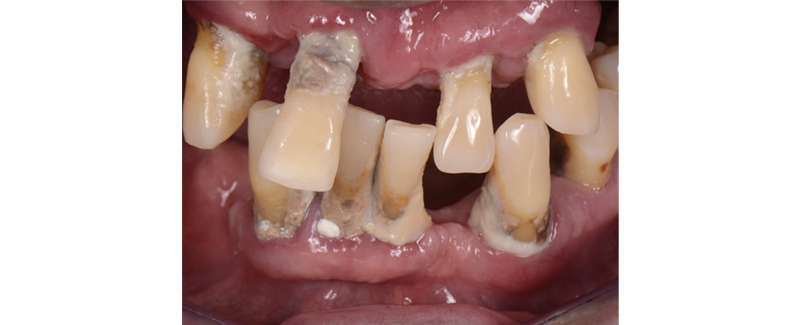

2. Advanced periodontal damage. (Fig. 2)